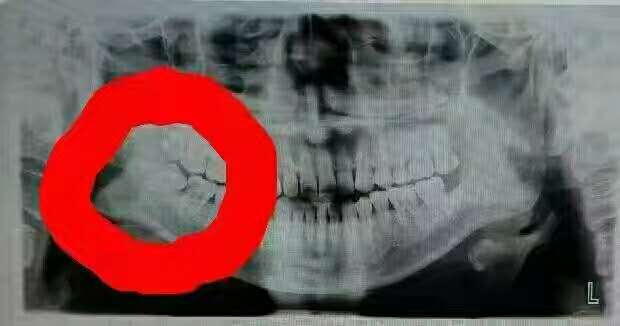

随着饮食的改变,越来越多的人牙齿出现了问题,最后不得不把牙拔掉。那么你知道拔牙后注意什么吗?

拔牙后注意八大事项